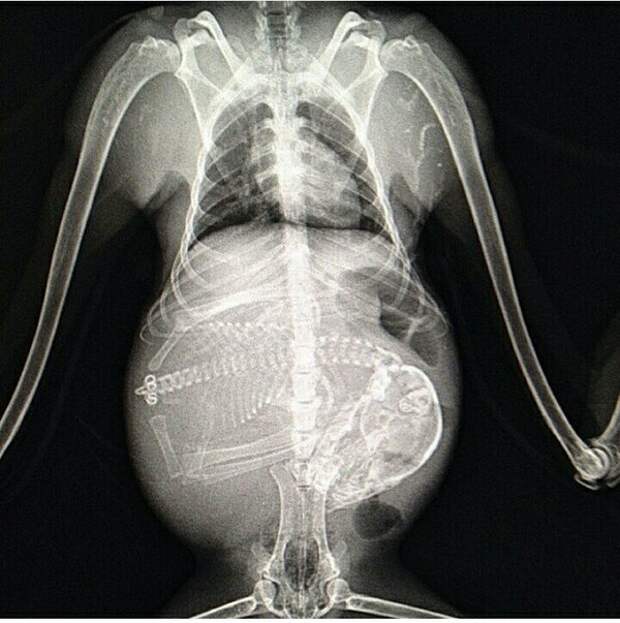

Беременная собака.